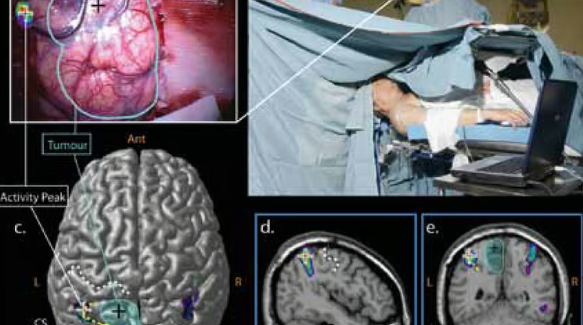

Computer-assisted navigation for precise brain and spine surgery, improving accuracy and patient safety.

Patient remains awake to monitor vital functions, allowing safe tumor removal near critical brain areas.